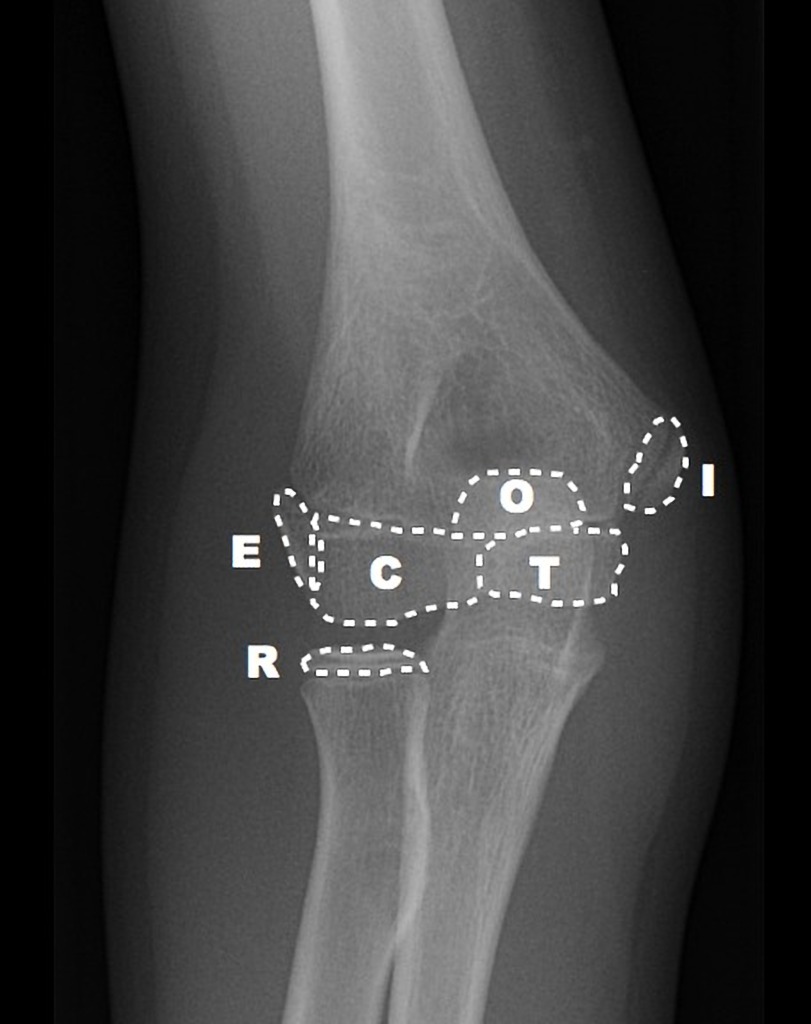

Order of elbow centres of ossification

A

• Capitellum

• Radial head

• Internal epicondyle

• Trochlea

• Olecranon

• External epicondyle

• Seen at 1, 3, 5, 7, 9, 11 years of age